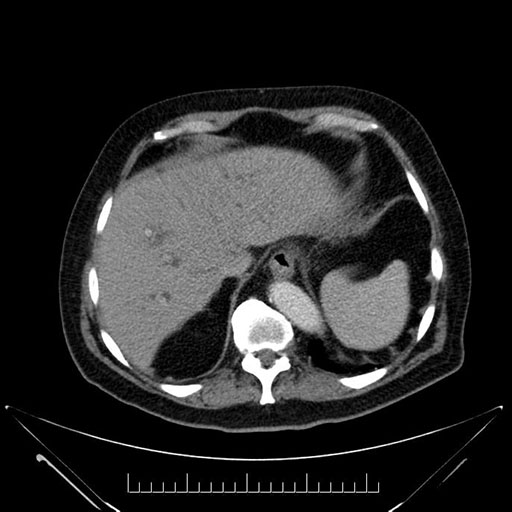

Imaging Analysis

Look through the patient's CT scan to identify any areas of concern for the necessary procedure.

Based on your CT findings, which issue(s) would give reason for "planned slowing down moment(s)" in this case?

Considering a standard Whipple procedure, what step(s) of the operation would you do differently in this case?